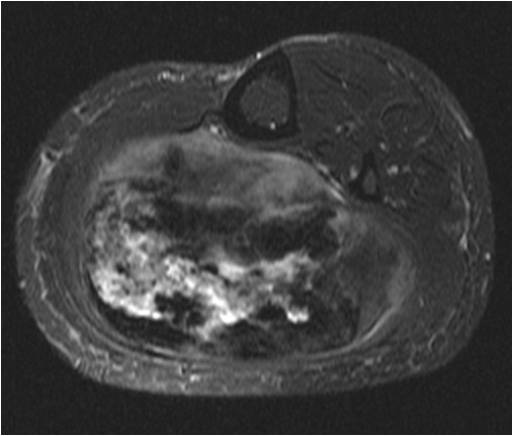

On radiographs, Low Grade Fibromyxoid Sarcoma presents as a discrete mass with soft tissue density without mineralization. MRI shows a well circumscribed heterogeneous mass, primarily hypo or isointense to muscles on T1-weighted image. The majority of tumors demonstrate heterogeneous signal intensity on T2-weighted images, correlating with the histological characteristics of low grade fibromyxoid sarcoma. Although 48 % of the patients demonstrate hyperintense signal and the rest of patients present admixed of hypo and Isointense signals (Fig. 1-5).

Fig. 3-5. MRI Axial (Fig. 3) and Coronal (Fig. 4) T2 –weighted fat-suppressed image heterogeneously high signal intensity areas admixed with hypo and isointense areas. T1-weighted post contrast fat-suppressed images (Fig. 5) show heterogeneous signal and enhancement within the tumor.